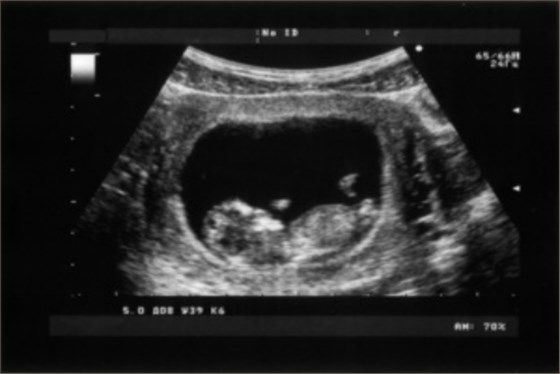

超聲科檢查NT即胎兒頸項透明層厚度,是用于檢查胎兒是否存在畸形的一項重要指標,可以排除早期出現的大結構畸形。NT檢查的正常值應該在2.5mm以內,如果NT檢查>2.5mm,提示NT值異常,常見于胎兒染色體異常、胎兒心臟功能異常、胎兒免疫性水腫等情況。

1、胎兒染色體異常:NT檢查一般在孕11-13周+6天進行,正常的NT值應<2.5mm。當NT值>2.5mm時,常提示胎兒可能存在染色體異常,如21-三體綜合征、18-三體綜合征、13-三體綜合征等。還可能存在其他染色體異常,如唐氏綜合征、性染色體異常等,也可能有先天性心臟病、腹壁疝等疾病;